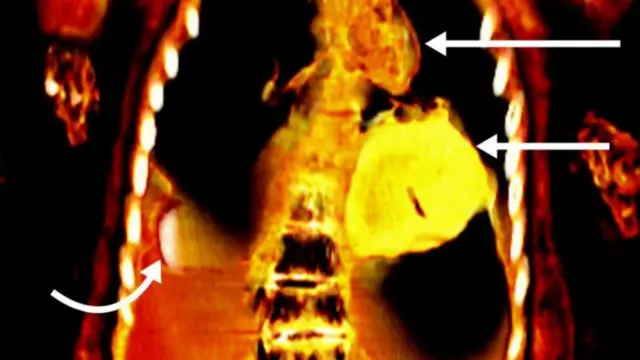

Chanzo cha picha, COURTESY SN SALEEM, SA SEDDIK, M. EL-HALWAGY

Picha hizo zilionyesha kuwa chini ya sanda zilizoufunika mwili wa kijana huyo kulikuwa na kitu cha urefu waa vidole viwili karibu na uume wa marehemu ambao haujatahiriwa, ulimi wa dhahabu mdomoni na moyo wenye umbo la mende pia uliotengenezwa kwa nyenzo hiyo ya thamanivambayo ilikuwa chini ya ya kifua.

Chanzo cha picha, SN SALEEM, SA SEDDIK, M. EL-HALWAGY

"Kompyuta inawakilisha maendeleo makubwa katika radiolojia. Badala ya kutumia picha moja, mamia ya makadirio ya sehemu nyembamba (vipande) vya mwili vinaweza kuunganishwa ili kuunda mfano kamili wa pande tatu, "alihitimisha.